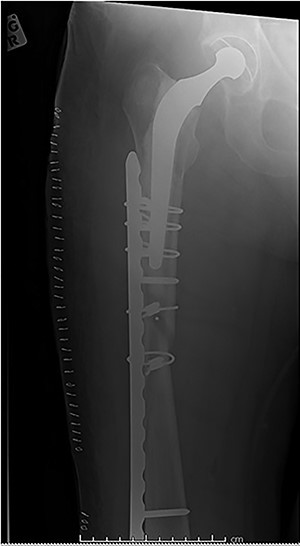

Case 4 (Figs 8–10): once again, screw placement too close to the fracture site has resulted in internal plate stresses exceeding its load-bearing capacity.

Inter-fragmentary screws have been utilized here. This lady may have benefited from placing an anterior bridging plate at the time of her original procedure if it was not possible to avoid this screw configuration.